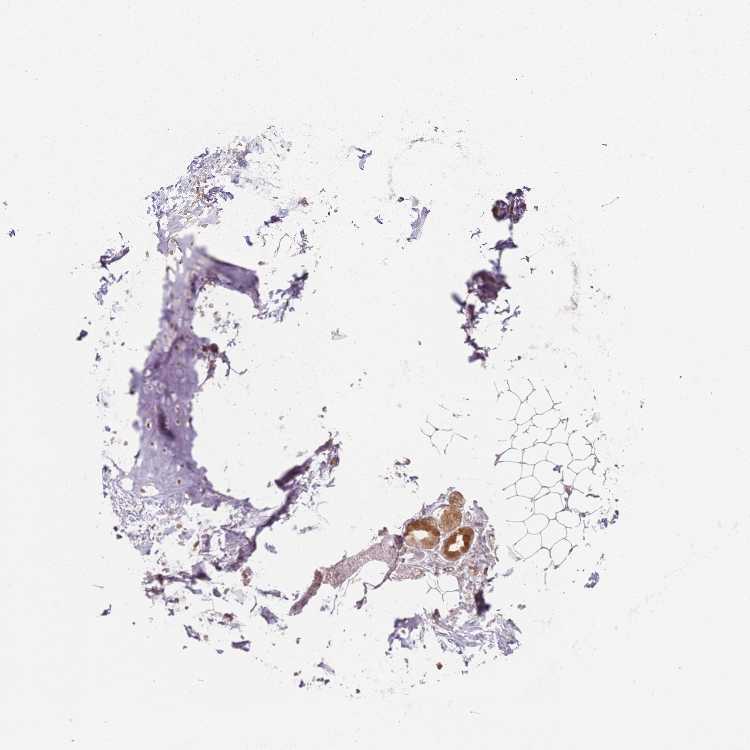

SOFT TISSUE 1 - Antibody stainingi

Antibody staining in the annotated cell types in the current human tissue is reported as not detected, low, medium, or high, based on conventional immunohistochemistry profiling in selected tissues. This score is based on the combination of the staining intensity and fraction of stained cells.

Each image is clickable and will lead to virtual microscopy that enables deeper exploration of all samples and also displays staining intensity scores, fraction scores and subcellular localization as well as patient and tissue information for each sample.

Antibody HPA048184Antibody HPA058793

Chondrocytes Low-

Fibroblasts Not detectedNot detected

SOFT TISSUE 2 - Antibody stainingi

Chondrocytes Not detected-

Peripheral nerve -Not detected